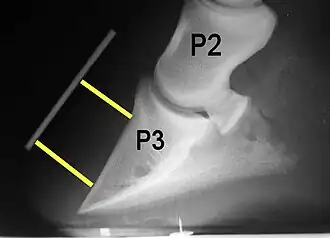

Radiographs are an important part of evaluating the laminitic horse. They not only allow the practitioner to determine the severity of the episode, which does not always correlate with degree of pain,[1] but also to gauge improvement and response to treatment. Several measurements are made to predict severity. Additionally, radiographs also allow the visualization and evaluation of the hoof capsule, and can help detect the presence of a lamellar wedge or seromas.[1] The lateral view provides the majority of the information regarding degree of rotation, sole depth, dorsal hoof wall thickness, and vertical deviation.[1][17] A 65-degree dorsopalmar view is useful in the case of chronic laminitis to evaluate the rim of the coffin bone for pathology.[1]

Several radiographic measurements, made on the lateral view, allow for objective evaluation of the episode.

- Coronary extensor distance (CE): the vertical distance from the level of the proximal coronary band to the extensor process of P3. It is often used to compare progression of the disease over time, rather than as a stand-alone value. A rapidly increasing CE value can indicate distal displacement (sinking) of the coffin bone, while a more gradual increase in CE can occur with foot collapse. Normal values range from 0–30 mm, with most horses >12–15 mm.[1]

- Sole depth (SD): the distance from the tip of P3 to the ground.

- Digital breakover (DB): distance from the tip of P3 to the breakover of the hoof (dorsal toe).[1]

- Palmar angle (PA): the angle between a line perpendicular to the ground, and a line at the angle of the palmar surface of P3.

- Horn:lamellar distance (HL): the measurement from the most superficial aspect of the dorsal hoof wall to the face of P3. 2 distances are compared: a proximal measurement made just distal to the extensor process of P3, and a distal measurement made toward the tip of P3. These two values should be similar. In cases of rotation, the distal measurement will be higher than the proximal. In cases of distal displacement, both values will increase, but may remain equal. Therefore, it is ideal to have baseline radiographs for horses, especially for those at high-risk for laminitis, to compare to should laminitis ever be suspected. Normal HL values vary by breed and age:[1]